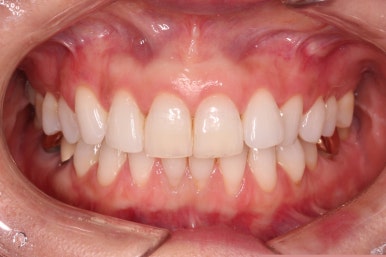

환자분이 원하시는 만큼 가지런해졌고, 부가적으로 생길 수 있는 부분들도 수용 가능한 선에서 잘 마무리가 되었습니다.

3개월이라는 빠른 기간 내에(심미보철 보다 약간만 더 긴 시간) 치아의 손상없이 마무리를 잘 했습니다.

물론 중간에 장치를 부착한 기간동안은 심미적으로 부담스러우셨겠지만요.

이상 부분교정과 앞니 심미보철을 고민하셨던 분을 연산동부분교정 잘 개선했던 치료사례였습니다.